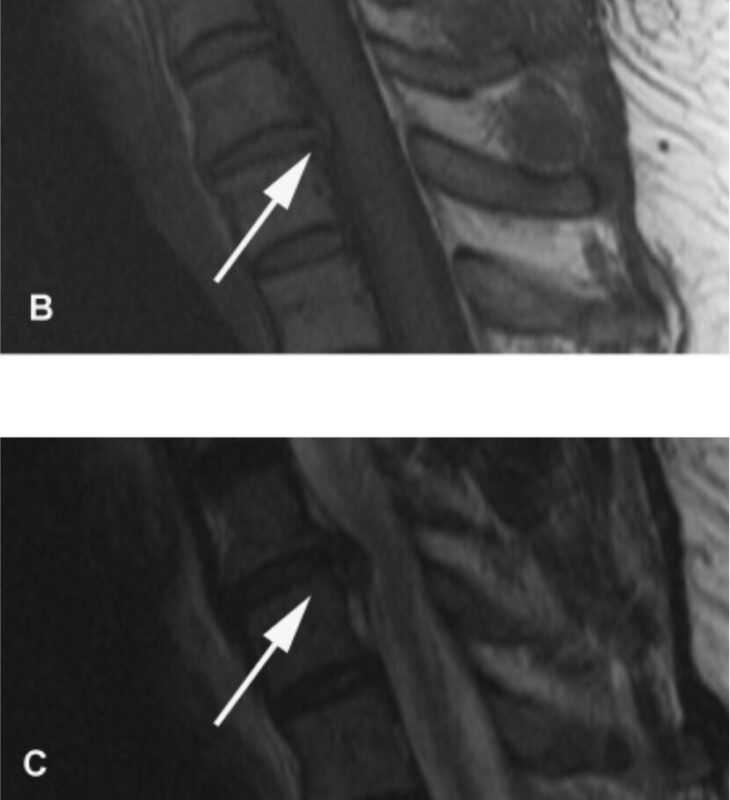

Nhìn chung, các kết quả lâm sàng gợi ý nhiều đến bệnh lý rễ thần kinh C7 bên phải và có thể ảnh hưởng nhẹ ở C6. Các nghiên cứu điện sinh lý đã xác định dẫn truyền vận động và cảm giác thần kinh trụ và thần kinh giữa bình thường ở bên phải và bên trái. Độ trễ sóng F dây thần kinh giữa và trụ bên phải và bên trái nằm trong phạm vi bình thường. Điện cơ kim của cơ tam đầu, nhị đầu, và cơ duỗi các ngón chung bên phải đều bình thường. Đánh giá cơ cạnh cột sống đã bị trì hoãn vì bệnh nhân bị đau. Chụp cộng hưởng từ cột sống cổ [Hình 1] xác định thoát vị đĩa đệm bên phải ở mức C6–7 gây ra hẹp nặng lỗ liên hợp thần kinh bên phải, không có chèn ép tủy sống đáng kể. Bệnh nhân được giới thiệu để cân nhắc phẫu thuật thần kinh lấy bỏ đĩa đệm C6-7.

Hình 1. Hình ảnh MRI cột sống cổ của bệnh nhân được mô tả trong bài này. Hình A là hình T2 đứng dọc cho thấy lồi đĩa đệm C6-C7 lấn vào khoang dưới nhện cổ. Hình ảnh B và C cho thấy đĩa lồi ra trên hình ảnh T1(B) và T2 (C). Có vết ấn nhẹ ở tủy sống nhưng không bị chèn ép đáng kể. Hình D là mặt cắt ngang của đĩa đệm thoát vị cho thấy giảm khoang dưới nhện lỗ liên hợp ở bên phải (mũi tên).